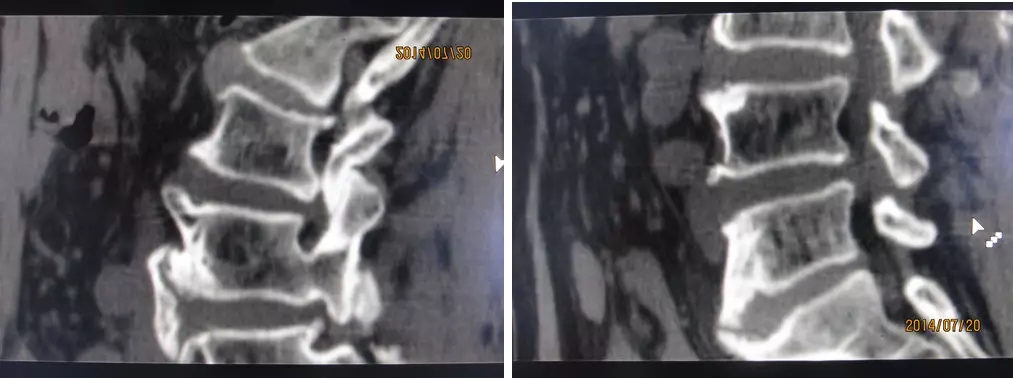

4.滑脱、峡部裂

腰椎前滑脱I度

椎弓峡部裂